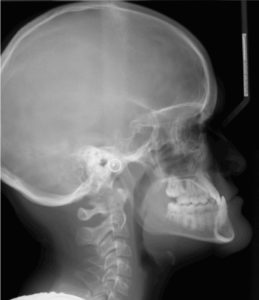

A 12.4 year old caucasian male presents with a chief complaint of “underbite and crooked teeth”